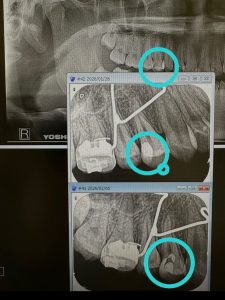

断髄

昨日、断髄した高校生

昨年CR充填から4か月経過、しみる、ズキ〰︎んと痛い

微小漏洩だね、代診医の治療🤪

除去、露髄、止血生理食塩水、サンメディカル社

MTAペーストにS.Bにマジェスティ 完全封鎖‼️

本日、全く痛みなし💪

もうひとつの症例は、根充後7年経過、病巣の消失💪